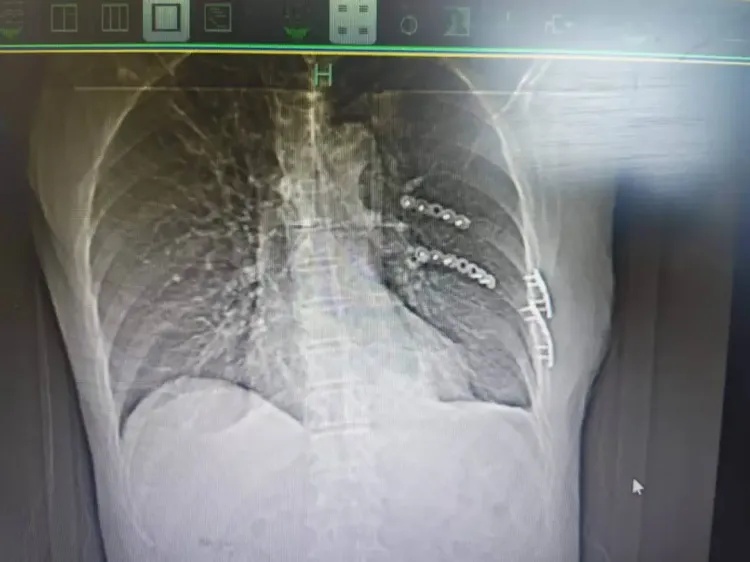

“患者被送到医院时,我们发现他共有13根骨头发生骨折,部分为单根多处断裂且合并左侧气胸。”接诊的杭州市富阳中医骨伤医院胸部创伤组莫军杰副主任医师对此感触很深,多发骨折会破坏胸廓稳定性,对中老年人而言更是“致命危机”:肋骨既是胸廓的保护支架,也是呼吸运动的助力器,一旦多根肋骨发生断裂,患者会本能地不敢深呼吸及咳嗽,这会导致肺部通气不足,痰液无法排出,进而引发肺部感染。

杭州市富阳中医骨伤医院供图

之后,医院迅速启动急救流程,经全面评估,莫军杰医生团队决定为裘叔进行手术,目的是固定骨折的肋骨,并通过引流排出胸腔内积血,解除疼痛并恢复正常呼吸功能。